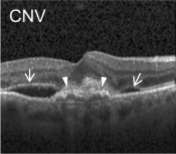

Eye diseases or ocular dysfunctions are fairly frequent in the general population, particularly among the elderly. The most significant anomalies in the eyes are choroidal neovascularization (CNV), diabetic macular edema (DME), and drusen accumulation in the macular region. In the recent decade, optical coherence tomography (OCT) has become one of the most rapidly evolving medical imaging technologies which can capture blood flow, polarization state, structural data, elastic properties, and molecular content, among other things, in biological tissues [1]. Optical diffraction and absorbance of biological tissues can be accurately measured with OCT and thus some diagnostic measures benefit from it.

Optical coherence tomography (OCT) images were selected from retrospective cohorts of adult patients from different hospitals around the world. OCT Images are labeled as (disease)-(randomized patient ID)-(image number by this patient) [11] and Fig 1 shows some examples of OCT images. Image properties are presented in Table II and the distribution of image quantity is presented in Table III. Custom image generators resize images to 224x224x3 and normalize them